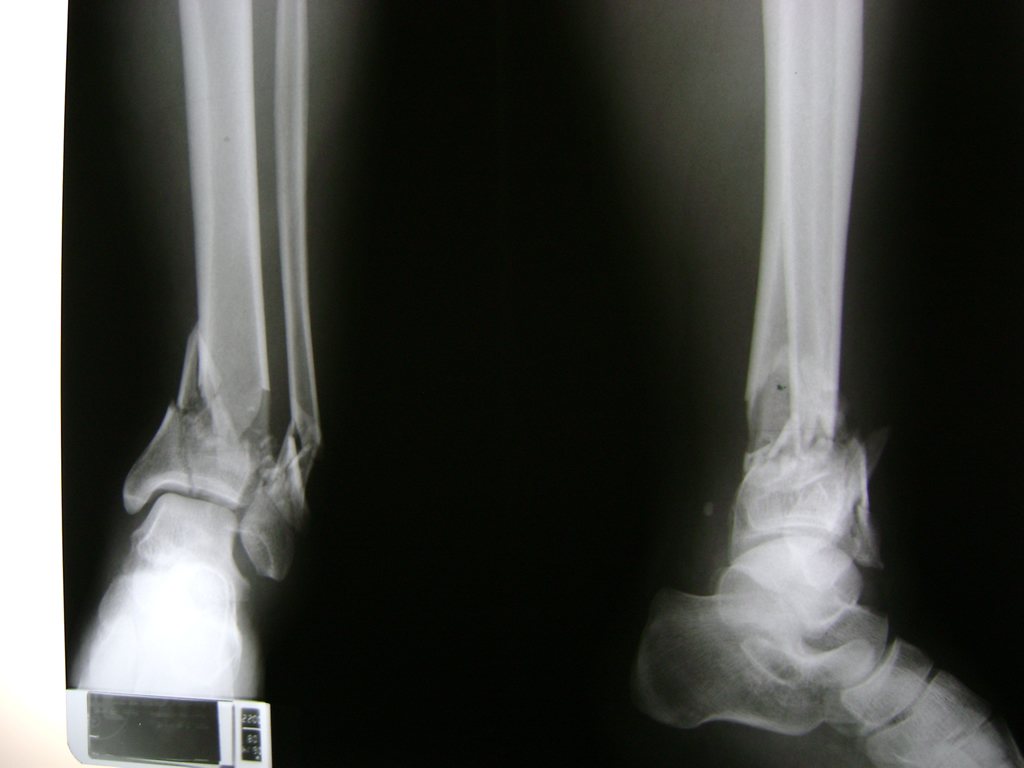

Una fractura de tobillo es la rotura de uno o más de los huesos del tobillo. Estas fracturas pueden ser:

- Parciales (el hueso está sólo parcialmente fisurado, no del todo).

- Completas (el hueso está perforado y está en 2 partes).

- Producirse en uno o ambos lados del tobillo.

Algunas fracturas de tobillo pueden requerir cirugía si:

- Los extremos de los huesos están desalineados entre sí (desplazados).

- La fractura se extiende hasta la articulación del tobillo (fractura intra-articular).

- Los tendones o ligamentos (tejidos que sujetan los músculos y los huesos entre sí) están rotos.

Cuando se necesita cirugía, es probable que esta implique el uso de clavijas de metal, tornillos o placas para sostener los huesos en su lugar mientras la fractura se consolida. Los elementos de soporte pueden ser temporales o permanentes.